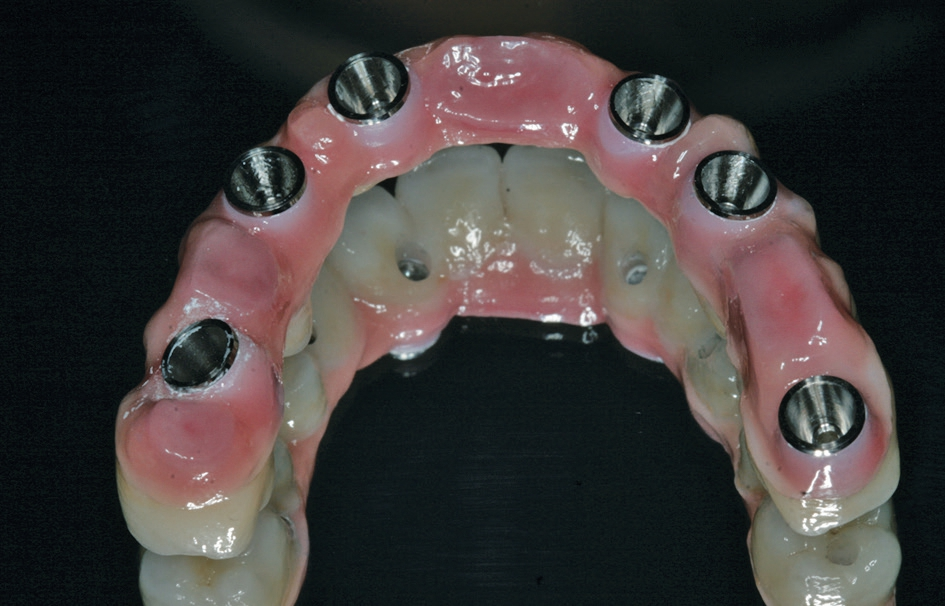

Nach einer initialen Abformung können vom Zahntechniker die optimalen Aufbauten nach der physiologischen Aufstellung und Wachseinprobe ausgewählt werden (Abb. 7 bis 9). Diese werden dann in die Implantate eingeschraubt und verbleiben dort, ohne dass sie wieder entnommen werden. Durch die Auswahl der Aufbauten vom Zahntechniker kann dort auch gleich eine Verblockung vorbereitet werden, mit der es möglich ist, die endgültig erreichte Position der angulierten Aufbauten direkt in das Labor zu übertragen. Somit stellt das Meistermodell eine identische Kopie der klinischen Situation dar. Dies ist notwendig, damit im Rahmen von CAD/CAM-Verfahren Gerüste für die weitere prothetische Versorgung gefräst werden [14]. Je nach Umsetzung der patientenindividuellen Aufstellung kann die definitive Versorgung hergestellt werden. Dort bestehen heute die Möglichkeiten der CAD/CAM-Technologien mit einem Titan- oder einem Keramikgerüst zur Verfügung. Sofern sich kein absolut passgenaues Gerüst erreichen lässt, kann dies durch eine Klebebasis kompensiert werden [5]. Dies wird in der Regel bei reinen Zirkonoxidgerüsten erforderlich. Im weiteren Ablauf kann die individuelle Charakterisierung der Vestibulärflächen und des Weichgewebsübergang erreicht werden (Abb. 10 bis 14).